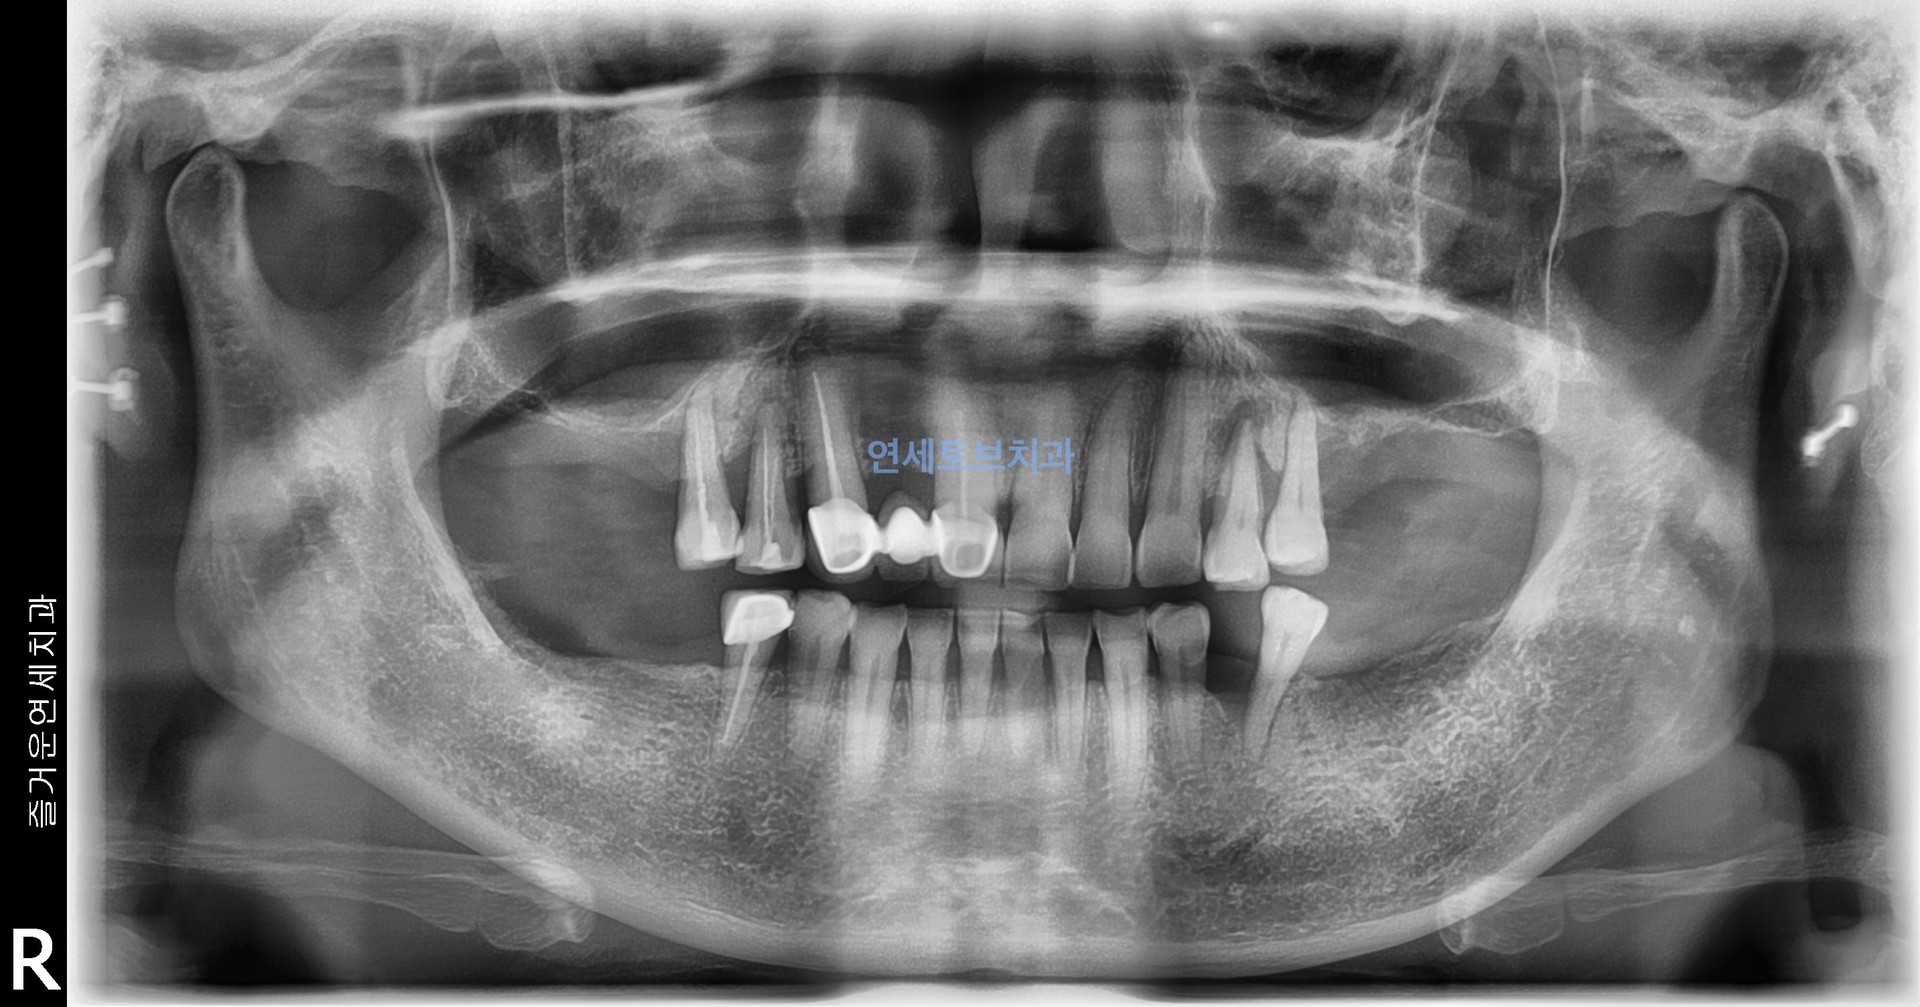

상악동 골이식술은 위턱 어금니(상악 구치부) 부위에 임플란트를 식립할 때,

치조골(잇몸뼈)이 부족한 경우 상악동(코 옆의 빈 공간) 점막을 들어올리고

그 공간에 뼈 이식재를 넣어 임플란트가 안정적으로 자리잡을 수 있도록 뼈를 보강하는 수술입니다

상악동 골이식술은 상악 어금니 부위 임플란트 식립에 필수적인 뼈를 확보하는 신뢰도 높은 술식으로, 치조골이 부족한 환자에게 임플란트의 성공률을 높여주는 중요한 수술입니다